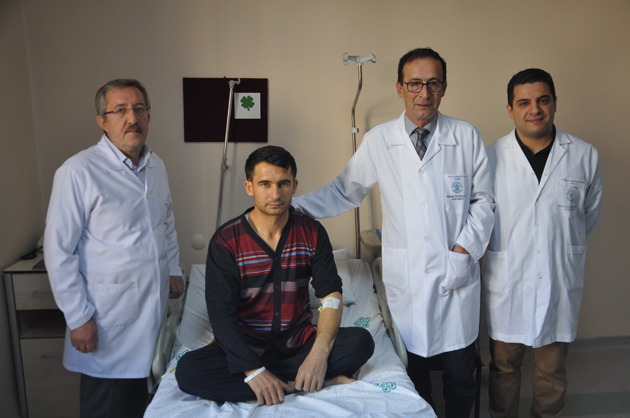

Hastanenin Cerrahi Tıp Bilimleri Üroloji Anabilim Dalı Öğretim Üyesi Prof. Dr. Ahmet Öztürk, Genel Cerrahi Anabilim Dalı Öğretim Üyesi Prof. Dr. Metin Belviranlı, Girişimsel Radyoloji Uzmanı Yrd. Doç. Dr. Süleyman Bakdık ve üroloji doktorlarından Yrd. Doç. Dr. Mehmet Giray Sönmez'den oluşan ekip, ultra mini cihazlarla karaciğere müdahale ederek taşları temizledi.

Necmettin Erbakan Üniversitesi Meram Tıp Fakültesi Hastanesi Cerrahi Tıp Bilimleri Üroloji Anabilim Dalı Öğretim Üyesi Prof. Dr. Ahmet Öztürk (sağ 2), Genel Cerrahi Anabilim Dalı Öğretim Üyesi Prof. Dr. Metin Belviranlı (solda) ve üroloji doktorlarından Yrd. Doç. Dr. Mehmet Giray Sönmez'den (sağda)